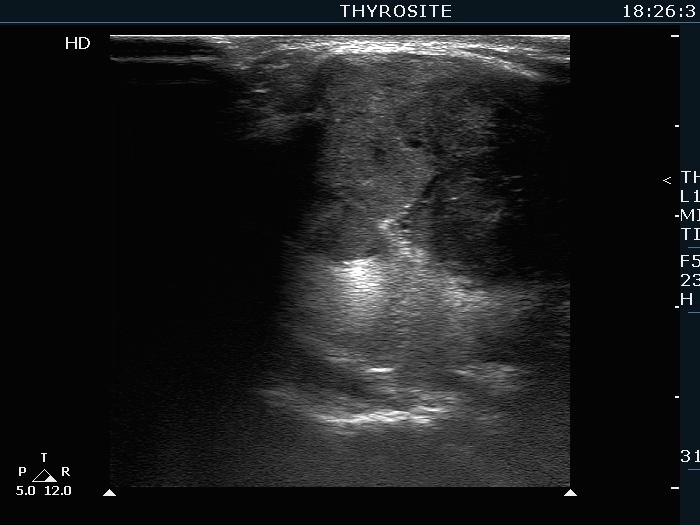

Extrathyroidal spread - case 2113 (ultrasonographic picture 5)

Isthmic part of the right lobe, longitudinal scan.